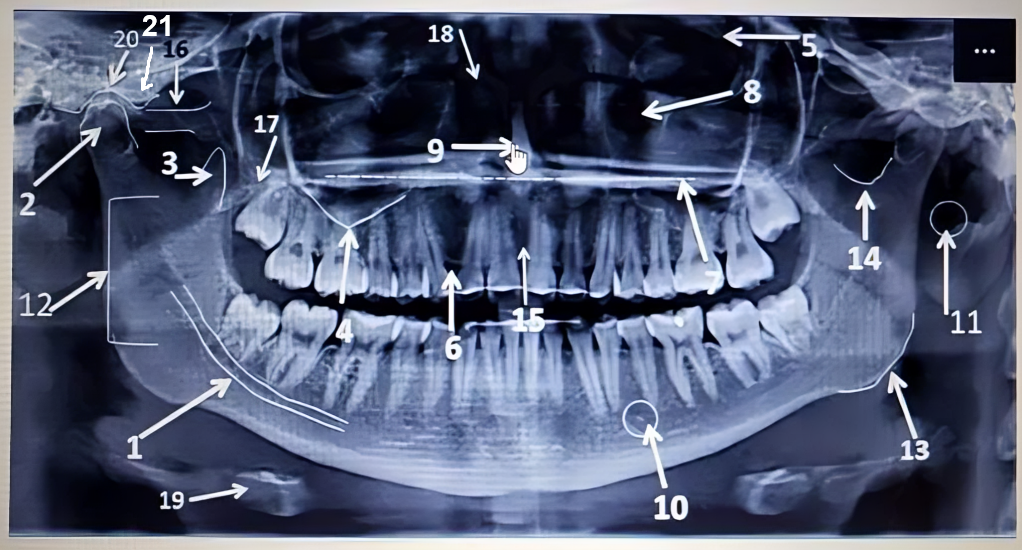

Identificar estructuras de panorámica - REAL

Identificar estructuras de panorámica

by Kevin David Sarmiento Reyes

1 2 3 4 5 6 7 8 9 10 11 12 13 14 15 16 17 18 19 20 21